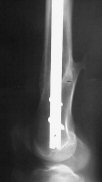

Attached are few examples from our Hospital:

Malpositioning is much too common (recurvatum, varus - valgus).

B. Fixation loosening: distal cutting of the nail, non-unions do happen (cases attached).

Locking Plating has more distal screws than any nail, fixed angles and provides much better fixation, especially in osteoporotic bone.